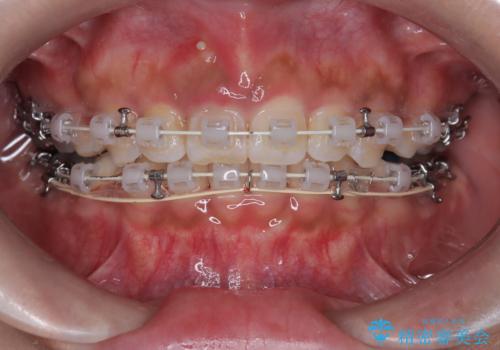

- 矯正装置

- 審美装置

- 患者様は、前歯の突出感を気にされて来院されました。診察の結果、歯列のスペースが不足しており、前歯を後方へ移動させるには抜歯が必要と判断。上下の小臼歯4本を抜歯し、目立ちにくい審美ワイヤー矯正(白いワイヤーと透明ブラケット)を使用して治療を行う計画を立てました。

抜歯によって前歯を下げるためのスペースを確保。その後、審美ワイヤー矯正を用いて、歯列全体のバランスを整えながら前歯を後方へ移動させました。治療後は、横顔のラインが整い、自然な口元になったことで、見た目も噛み合わせも改善しました。患者様からは「口元がすっきりして、自信を持って笑えるようになった」と喜びの声をいただきました。